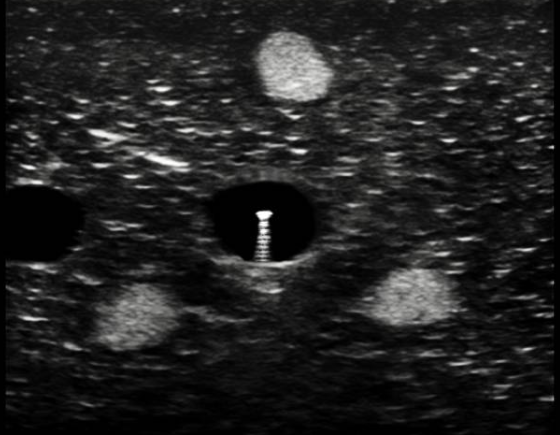

平面外穿刺的超声图像,图中亮点为针尖。

平面内穿刺的优势在于整个针体(包括针尖)可视化,但是对操作者手法技巧(始终保持探头长轴与血管长轴平行)要求较高,易受解剖结构限制。